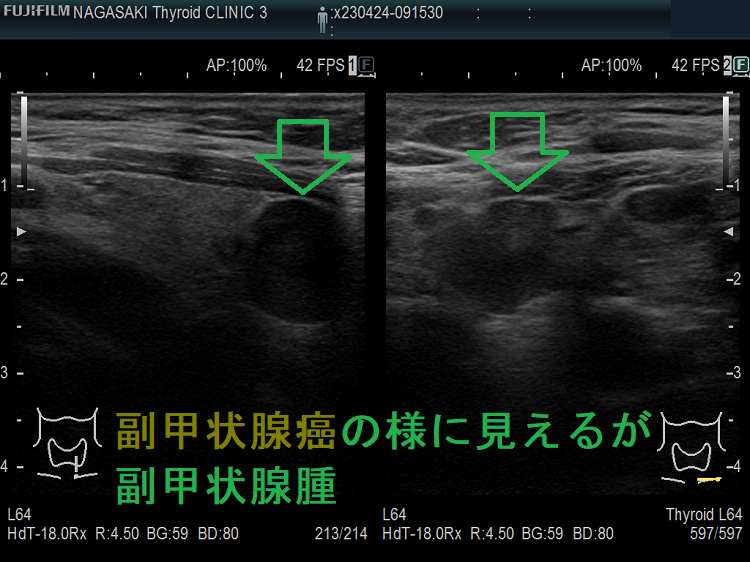

甲状腺内副甲状腺腫は、超音波(エコー)検査で甲状腺腫瘍と形態的に鑑別できない場合があります(実際は下の写真のように診断できていますが・・)。特徴的な超音波(エコー)所見は、腹側の高エコーで感度86%、特異度100%です[Surgery. 2012 Dec;152(6):1193-200.]。さらに、99m-Tc MIBIシンチグラフィーで取り込み(集積)があれば甲状腺内副甲状腺腫と診断できます。

腺腫様甲状腺腫に合併する甲状腺内副甲状腺腫

腺腫様甲状腺腫に合併する甲状腺内副甲状腺腫は、腺腫様結節と鑑別が難しいだけでなく、多腺性(5-6腺)のケースがあります。

副甲状腺腺腫と同じような位置(写真では左甲状腺の背側)にあり、甲状腺の中なのか外なのかはっきりしません。副甲状腺腺腫のように見えるも、実は甲状腺の中にある甲状腺腺腫様結節。その他、排液後の甲状腺腺腫様結節も副甲状腺腺腫と同じように見える場合もあります。